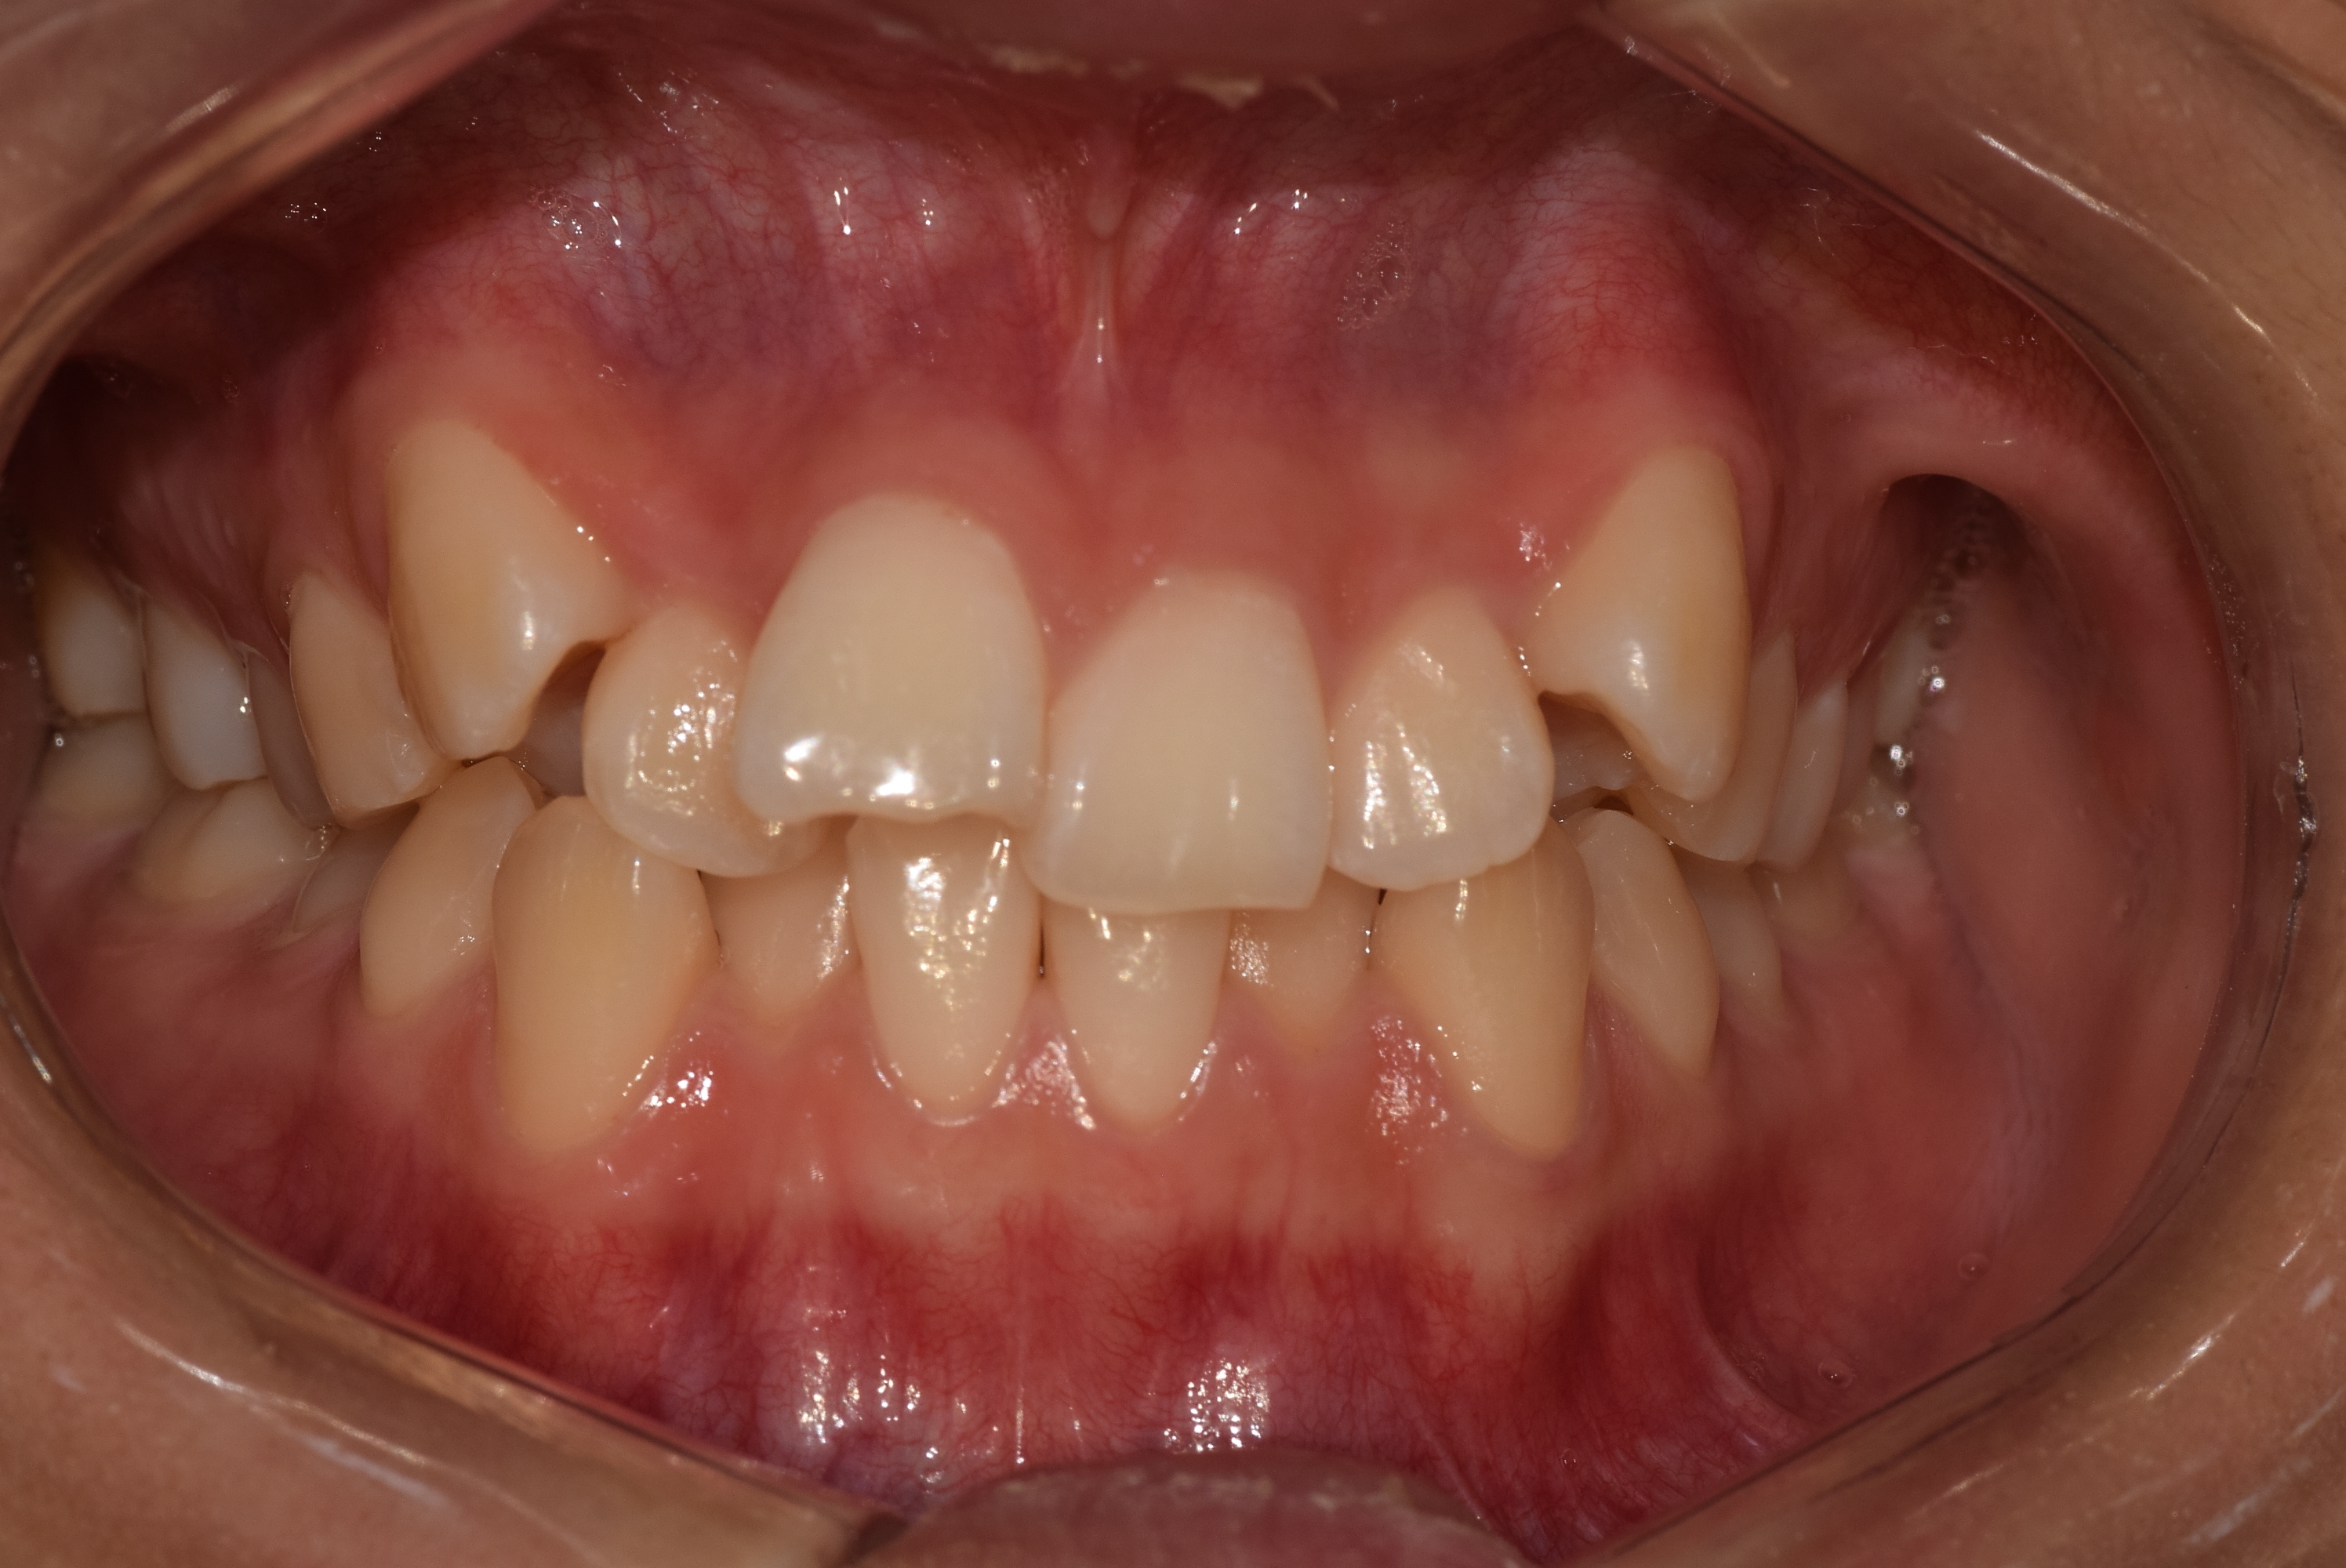

[치아교정] 제목 : (교정)비발치 총생 치료

심한 총생에서도 발치 없이 교정치료